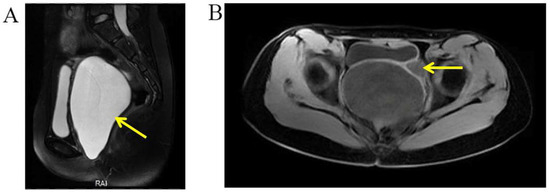

A three-dimensional transvaginal ultrasound revealed adenomyosis and a septate uterus (Figure 1). Two cystic masses with thick internal fluid measuring 3.7 × 4.2 × 2.7 cm (Figure 1A) and 7.5 × 3.1 × 2.1 cm (Figure 1B) were seen on the right side of the uterus, respectively. These cystic masses were considered to be a hydroureter with vaginal fistula. A urinary tract ultrasound revealed the absence of a right kidney, as well as a dilated right ureter measuring 11.1 × 1.8 cm with an ectopic opening into the right vagina (Figure 2A). A computed tomography urography (CTU) revealed the absence of the right kidney (Figure 2B). A pelvic MRI showed a cystic mass considered to be a mesonephric cyst on the right side of the pelvis, bladder, and urethra (Figure 3A). A complete septate uterus with multiple fibroids was also found (Figure 3B). The creatinine concentration of the fluid inside the pelvic cyst was measured to be 157 nmol/L via transvaginal aspiration (Figure 4).

Figure 3.

Selected MRI images of the pelvis. (A) Pelvic MRI showed a fluid-filled cyst (yellow arrow) along the right side of the pelvis, bladder, and urethra (mesonephric remnants). (B) Pelvic MRI showed a complete septate uterus with multiple fibroids (yellow arrow).

A 14-year-old girl was admitted to the department of gynecology due to monthly cyclic pelvic pain. A pelvic examination showed an imperforate hymen. A rectoabdominal examination showed a cyst 10 cm in diameter palpated in the pelvis. Additionally, the bottom edge of the cyst was located 1 cm away from the vaginal opening. The needle aspiration fluid through the hymen revealed values of 5213.2 μmol/L for creatinine and 39.63 mmol/L for urea. An abdominal MRI revealed a left pelvic cystic mass, left hematosalpinx, and left kidney atrophy (Figure 6). The pelvic MRI demonstrated that the fluid-filled vagina was highly dilated, and the left dilated ureter drained into the vagina (Figure 7). An ascending urography also revealed a left ectopic ureter. After the incision of the imperforate hymen, 500 mL of pale-yellow purulent pus drained from the vagina. After an antibiotic treatment, a laparoscopy and hysteroscopy were performed. The surgical procedures revealed a double primordial uterus measuring 2.5 × 1.9 cm on the right and 3.0 × 1.5 cm on the left, but no cervix. Bilateral ovaries and fallopian tubes were normal. The patient’s vagina was unobstructed. An opening orifice of the left ureter, with a diameter of 0.2 cm, was seen in the vagina. Subsequently, the left atrophic kidney and the irregularly enlarged left ureter were removed to prevent future leakage and infection. In summary, the left ectopic ureter opened into the vagina, causing fluid leakage into the vagina. Due to the imperforate hymen, urine accumulated inside the vagina, which led to vaginal dilatation, infection, and pelvic pain.

Figure 7.

Selected MRI images of the pelvis. (A) Pelvic MRI demonstrated a highly dilated vagina with internal fluid measuring 10.2 × 7.3 × 13.2 cm (yellow arrow). (B) Left ureter was dilated (yellow arrow), and the ectopic orifice of the left ureter was located at the vagina.